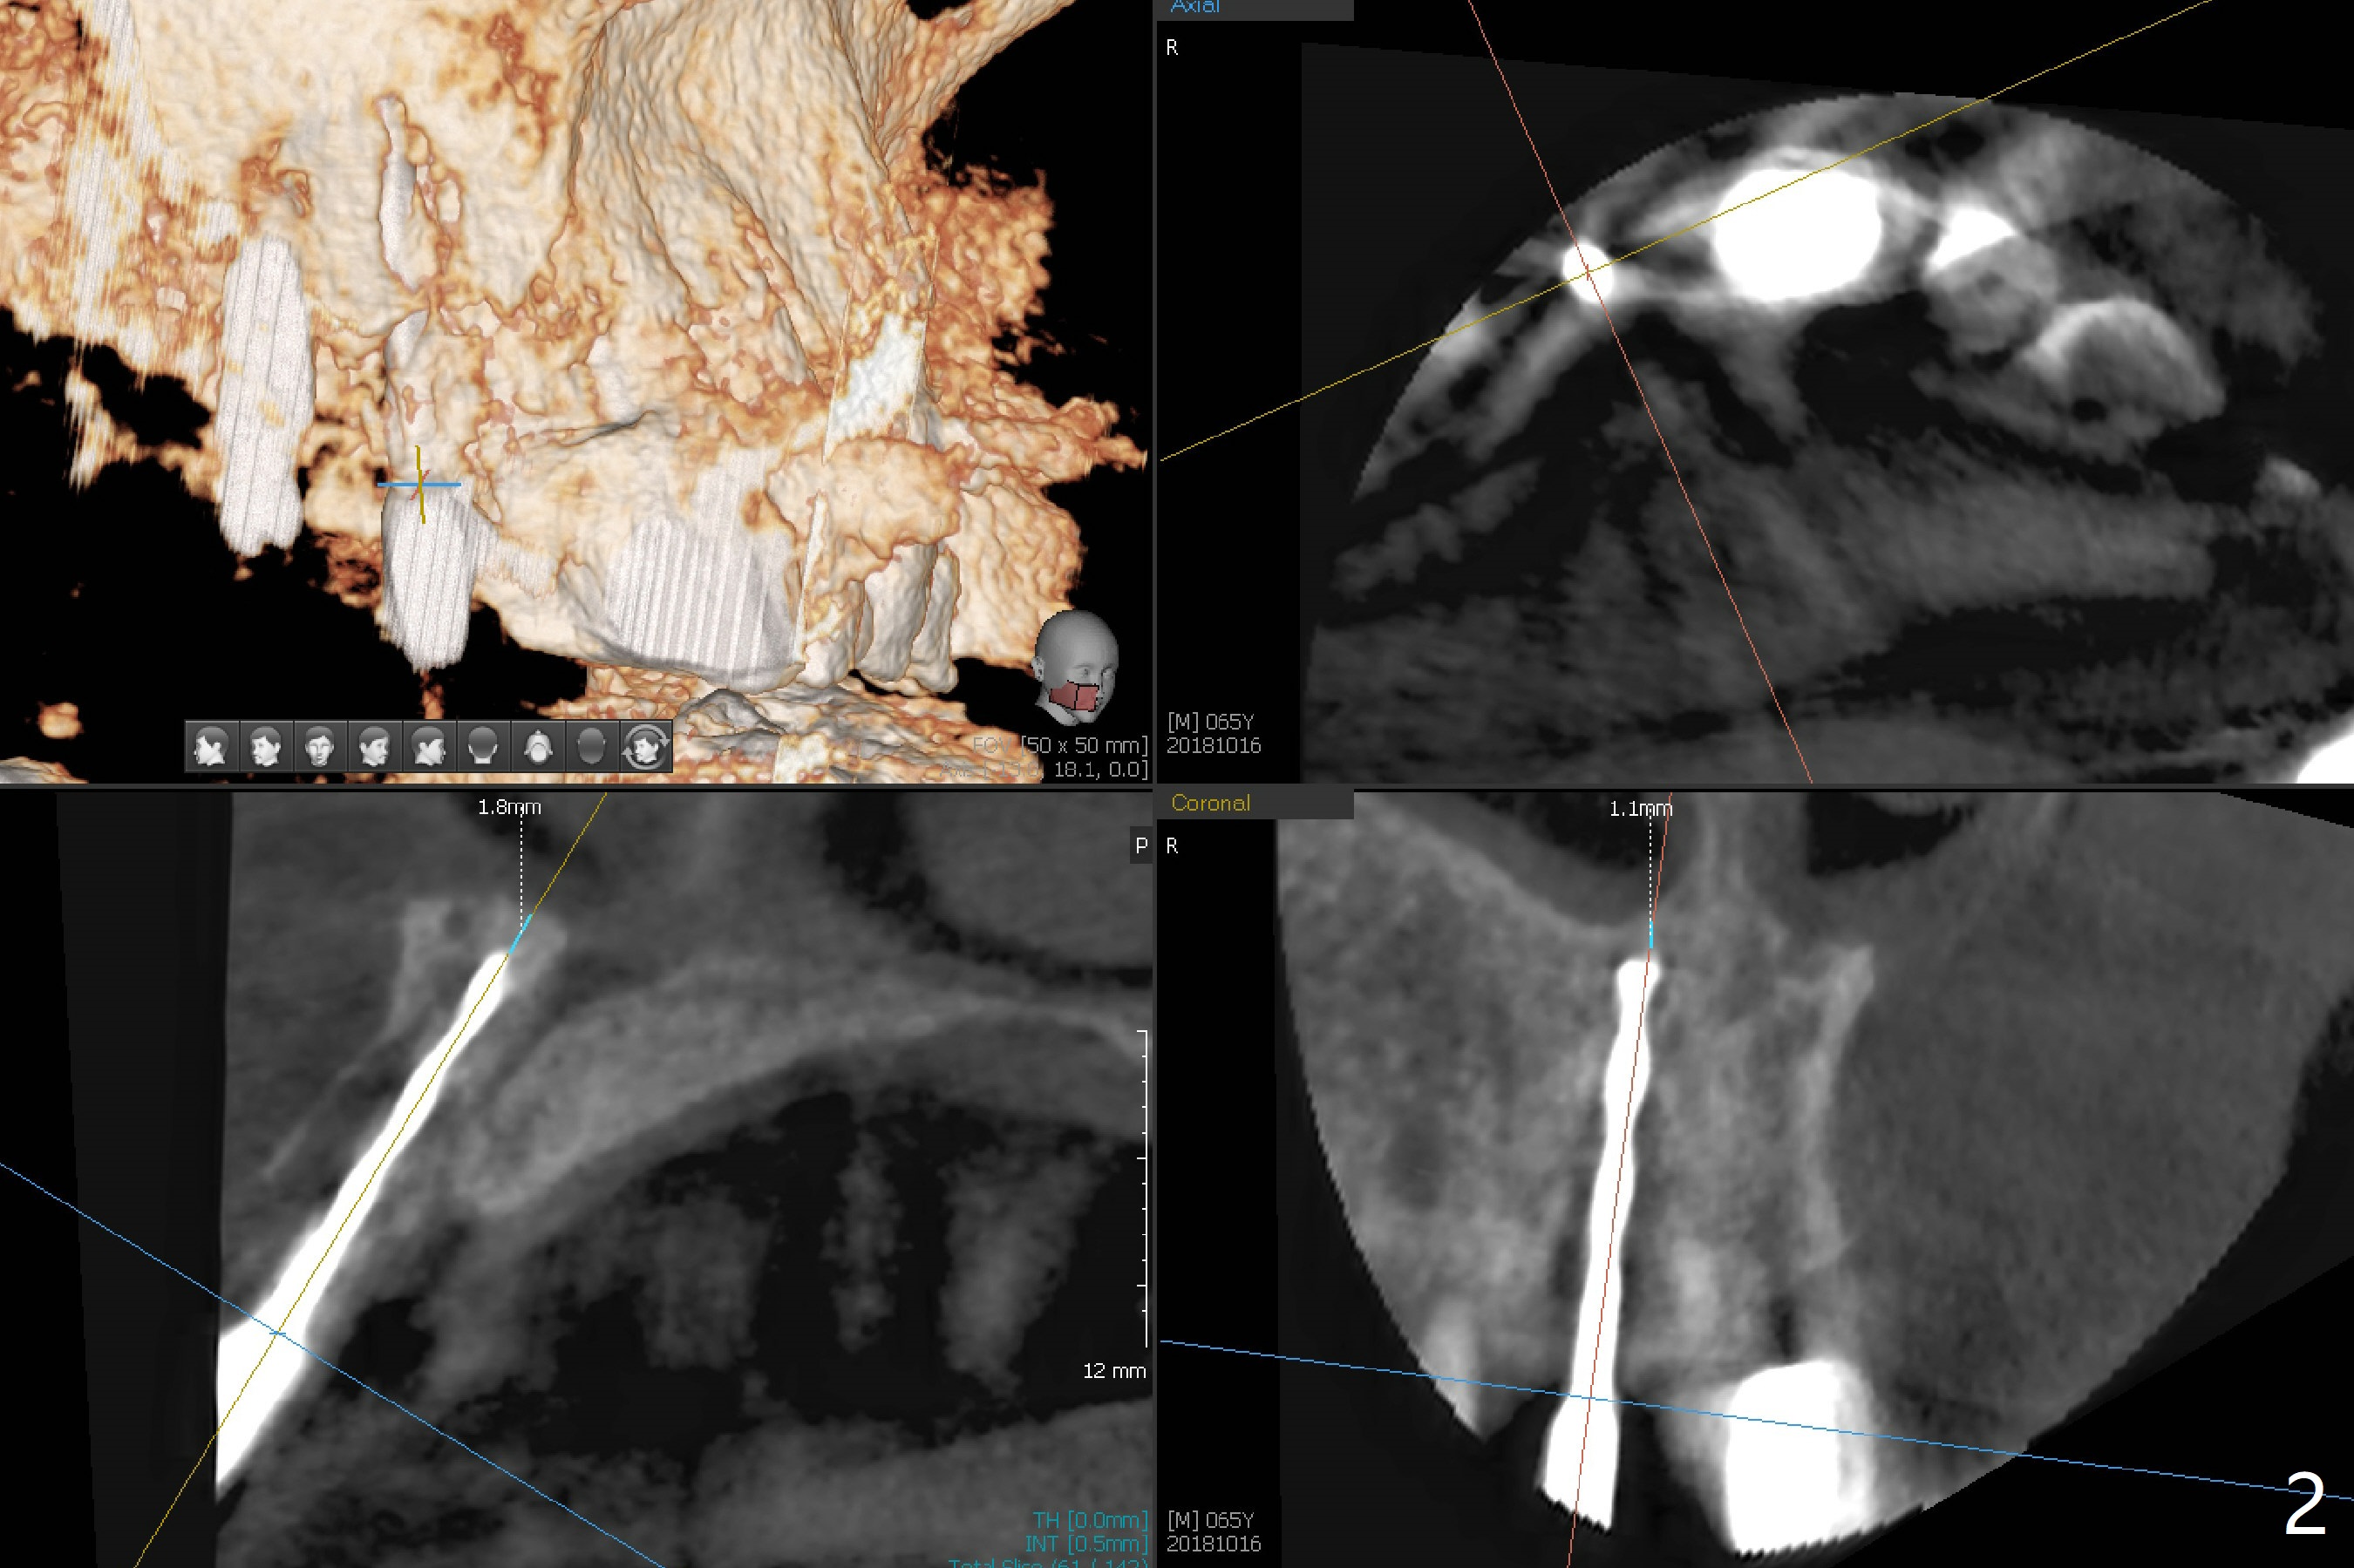

Reanalysis of preop CBCT shows a longer implant (3x16mm, green) to be placed palatal should be able to solve buccal plate bone loss associated with the previous 3x14 mm one at #8 (Fig.1). After crown/implant removal (with ease), a new palatal osteotomy is initiated flapless with 1.2 mm drill for 16 mm (palatal gingival margin, Fig.2). Following 1.5 mm drill for ~ 17 mm, a 3x16(2) mm 1-piece implant is placed >40 Ncm (Fig.3). After bone graft through limited access and abutment preparation, an immediate provisional is fabricated with clearance. The provisional dislodges repeatedly, mainly due to palatal perforation. It gets lost while the patient travels to his home country. Although there seems to be bone loss around the implant 2.5 months postop (Fig.4), the gingiva looks healthy. A new provisional is fabricated without impression. Because of short vertical height and small abutment diameter as well as bruxism, the provisional easily dislodges. The patient will return for impression 4 months 10 days postop. The bone loss remains 4 months postop when impression is taken (Fig.5).